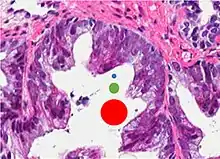

77%[notes 2] | 54%[notes 2] | ![]() |

| Non acinar (or mixed acinar/ non-acinar) adenocarcinoma | Ductal adenocarcinoma | 3% to 12.7%[8][notes 1] | ![]() |